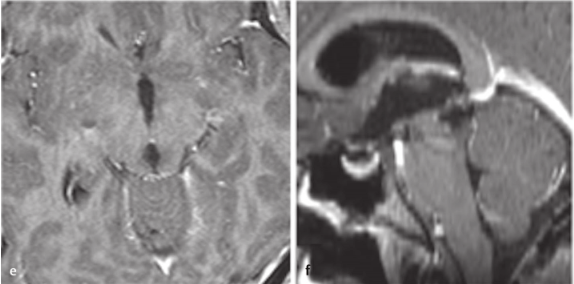

45岁的张先生突然遭遇剧烈头痛、喷射状呕吐,很快陷入意识模糊——这是颅内压急剧升高的危险信号!医生立即为他实施神经内镜下脑室造瘘术,暂时缓解了这场生死危机。

进一步检查发现更严峻的挑战:脑干肿瘤已从“生命中枢”向上侵袭至第四脑室。如果从小脑上部进入,手术深度难以超过2厘米,想要全切肿瘤几乎是不可能的任务!

面对这一“手术禁区”,巴教授采用“一台手术,双入路”的精准策略。通过多方位精准打击,在保护神经功能的同时,实现了肿瘤的最大程度切除,为患者赢得了生存希望!

手术入路图解

术后MRI

术后病理显示形成菊形团的胶质神经元肿瘤(RGNT),这位男士术后随访已达15年!